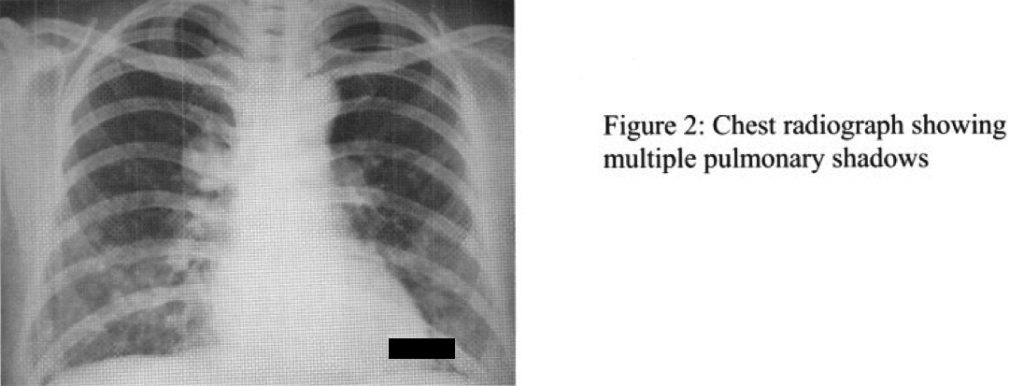

The patient was a non-smoker and non-drinker working in a garment factory. She had history of uterine tumour with operation done in 1984. She presented with vague chest discomfort for one month. Private chest X-ray showed multiple lung shadows (Figure 2). Physical examination was unremarkable except for the abdominal surgical scar. There were no palpable lymph nodes, breast lumps or thyroid nodules.

The patient was a non-smoker and non-drinker working in a garment factory. She had history of uterine tumour with operation done in 1984. She presented with vague chest discomfort for one month. Private chest X-ray showed multiple lung shadows (Figure 2). Physical examination was unremarkable except for the abdominal surgical scar. There were no palpable lymph nodes, breast lumps or thyroid nodules.